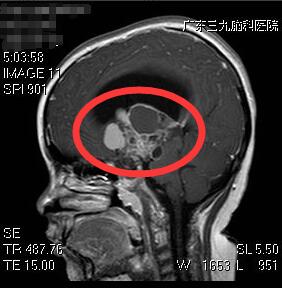

肿瘤切除前

为进一步确诊,刘女士带着小敏前往广东三九脑科医院就医。据该院副院长、神经外五科主任鲁明介绍,患者体型肥胖,有68斤,身高偏矮,只有121厘米,头颅磁共振检查提示鞍区占位性病变,结合其它临床症状及相关检查,考虑为颅咽管瘤可能性大。

5月22日,鲁明主任为患者在全麻下行巨大颅咽管瘤切除术。因肿瘤巨大,包裹了颈内动脉、大脑前动脉和中动脉,且位于脑深部,钙化明显,质地坚韧,故手术难度极大。最终,经医生近12个小时的奋战,肿瘤顺利切除。目前,小敏康复良好。